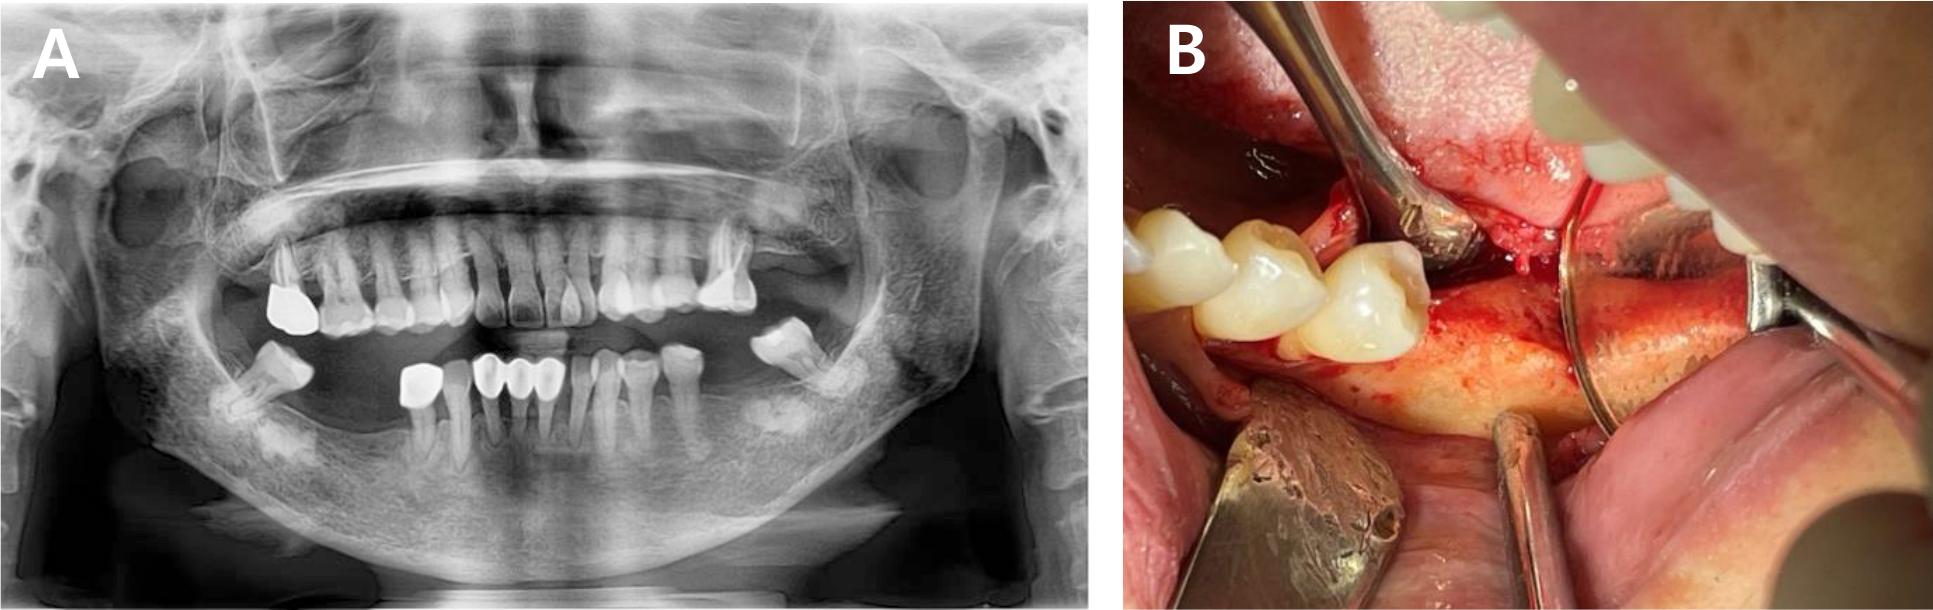

A 63-year-old female with no significant systemic medical history visited our clinic for implant placement at the mandibular left first premolar, which had been extracted 4 months earlier due to dental caries. Preoperative clinical and radiographic examination revealed a flat residual ridge with a steep buccal slope. Ideal prosthetically driven implant placement resulted in buccal thread exposure, necessitating simultaneous HRA (Fig. 1).

To compensate for the anticipated horizontal deficiency of approximately 1.5 mm, bone grafting was planned using a combination of dehydrated ADM (MegaDerm® thickness: 0.3–0.6 mm; L & C Bio, Seoul, Korea) loaded with rhBMP-2 (Novosis®; CGbio, Seoul, Korea).

Under local anesthesia with 2% lidocaine, a crestal incision was made and a full-thickness mucoperiosteal flap was elevated. A 3.5 mm diameter implant was placed according to prosthetic considerations, followed by cover screw installation. As expected, the buccal threads were exposed immediately after placement. The ADM was trimmed to fully cover all areas where buccal bone thickness was clinically less than 1.5 mm, and then immersed in 0.25 mg rhBMP-2 dissolved in 0.5 mL of normal saline for 1 min. The soaked ADM was folded once, directly applied to the defect site, and secured with simple interrupted sutures (Fig. 2).